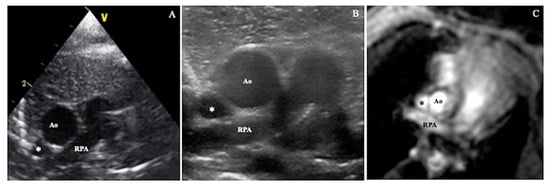

SVC area was assessed directly from an axial/short axis view, at the level of the RPA, using high-definition zoom, with a 10 MHz sector probe. Maximum and minimum cross-sectional areas through the cardiac cycle were measured offline from the B mode images (Figure 2A).

SVC flow velocity was assessed from a suprasternal view following the SVC from its origin at the innominate vein confluence to the right atrium. Angle correction of flow velocity was not used. The PWD gate was placed at the level of the RPA. VTI was calculated offline from SVC peak velocity (Figure 3).

SVC area was assessed directly from an axial/short axis view, at the level of the RPA as in Method 2, but in this case using a high frequency linear probe (12 MHz). Maximum and minimum area through the cardiac cycle were measured offline from the B mode images (Figure 2B).

Figure 2. SVC cross-sectional area assessed by: (A) sector probe according to Method 2, (B) high frequency linear probe according to Method 3, (C) phase contrast magnetic resonance imaging. Ao = aorta, RPA = right pulmonary artery, * = superior vena cava.